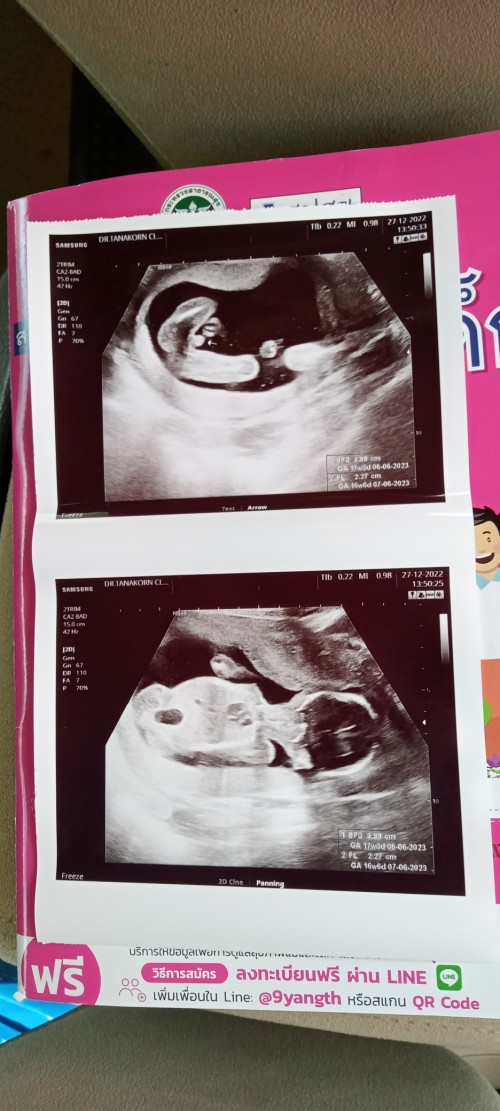

แม่ๆกำหนดคลอดวันที่เท่าไหร่กันบ้างค่ะ กำหนดคลอดบ้านนี้ 06/06/2566 ค่ะ #ทีมมิถุนายน #ทีมชาย